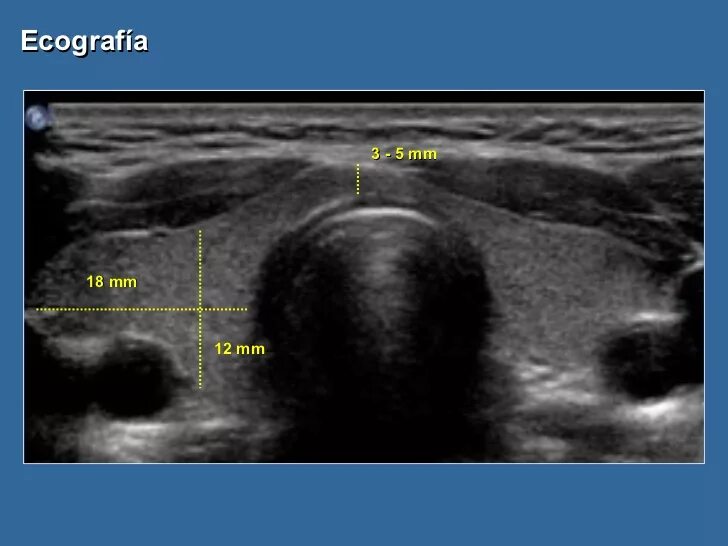

Диффузные изменения щитовидной железы tirads 2